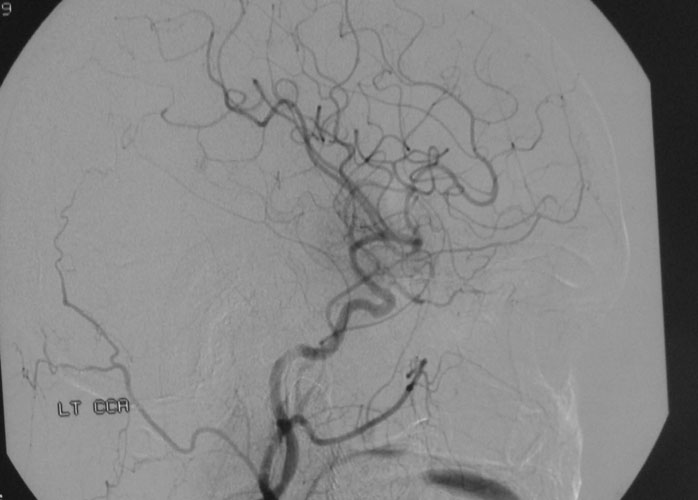

Arteriovenous malformations

Arteriovenous malformations of the brain are abnormal bunch of blood vessels that can rupture causing bleeding, or may cause seizures. Brain imaging (CT, MRI) is required for early diagnosis, while definitive treatment is carried out after cerebral angiography. Treatment implies craniotomy and excision of the AVM, which can be done safely in majority of the cases. Embolisation and radiosurgery are acceptable substitutes, but carry risk of further bleeding.